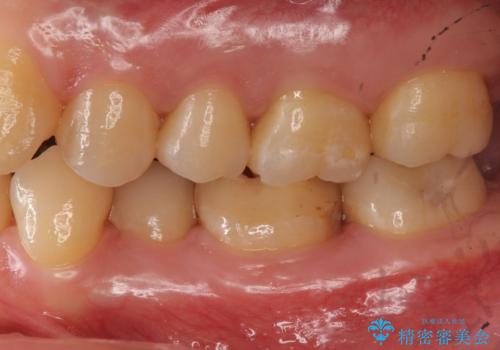

- 左下6 仮歯+セラミッククラウン 11000円+110000円費用は治療当時の料金となります

樹脂の材料はどうしても変色などの劣化スピードが速いです。

樹脂の変色が気になる場合は、劣化しにくいセラミックに材料ごと変えることをお勧めします。